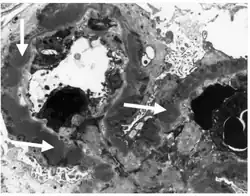

Subepithelial dense deposits and basement membrane reaction arrows

Immune complexes (black) are deposited in a thickened basement membrane creating a "spike and dome" appearance on electron microscopy.

- By light microscopy, the basement membrane is observed to be diffusely thickened. Using Jones' stain, the GBM appears to have a "spiked" or "holey" appearance.

- On electron microscopy, subepithelial deposits that nestle against the glomerular basement membrane seems to be the cause of the thickening. Also, the podocytes lose their foot processes. As the disease progresses, the deposits will eventually be cleared, leaving cavities in the basement membrane. These cavities will later be filled with basement membrane-like material, and if the disease continues even further, the glomeruli will become sclerosed and finally hyalinized.